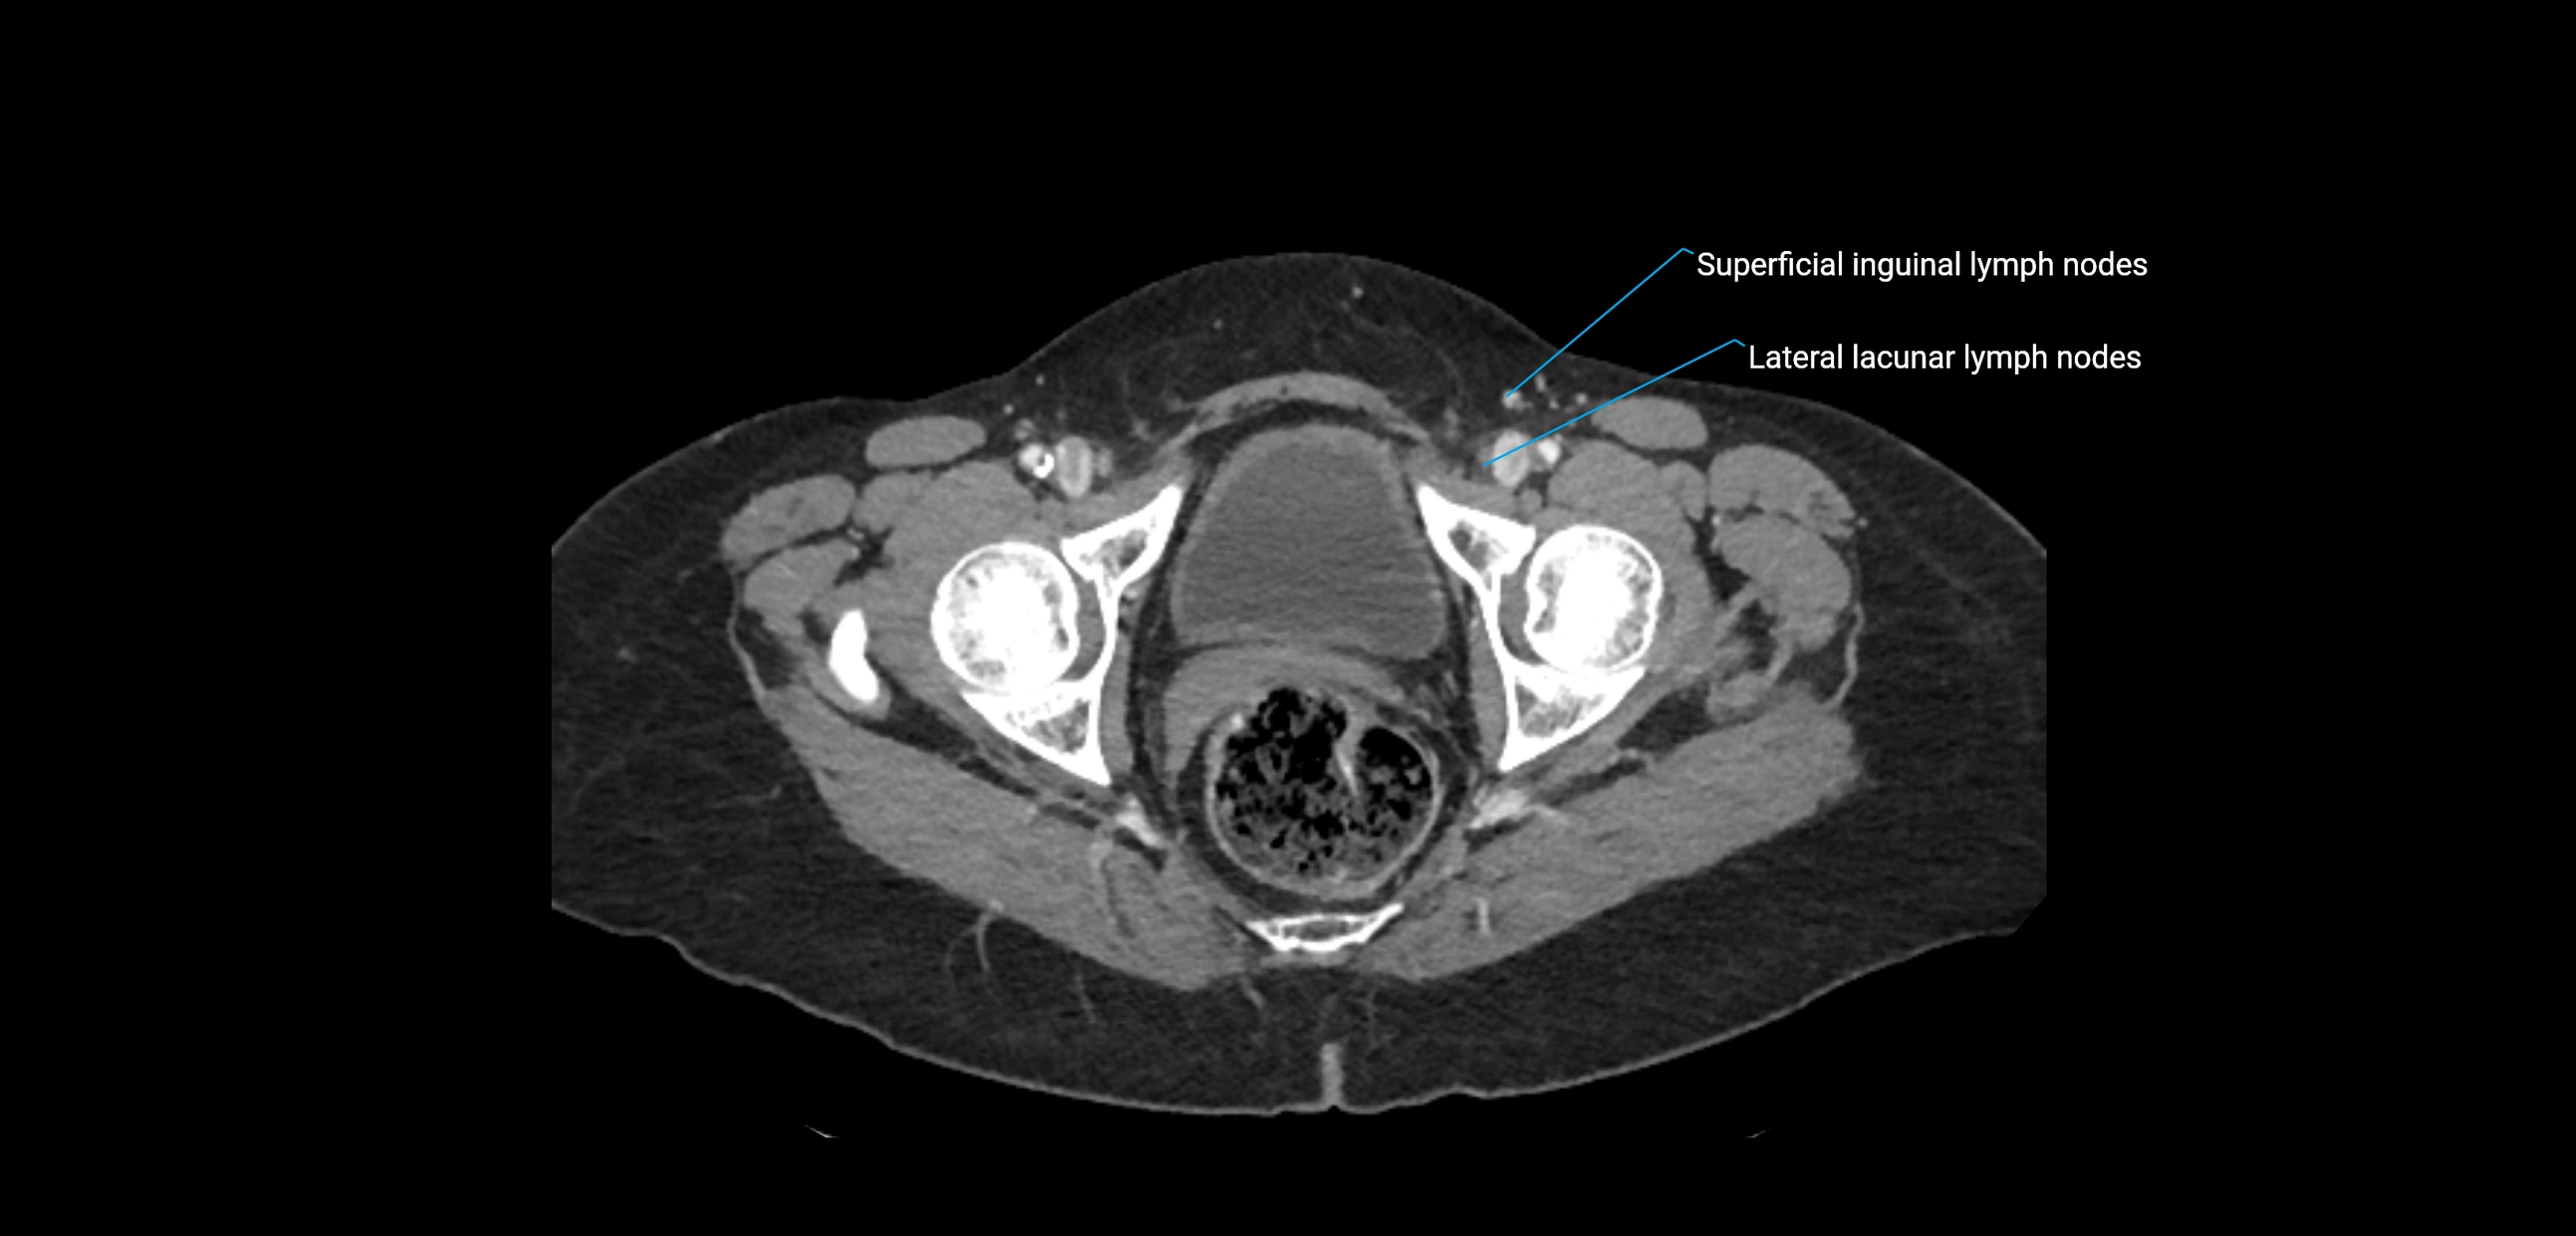

MRI images

image